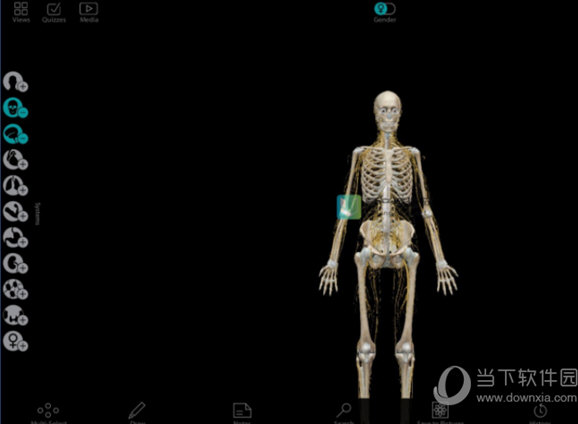

1、双击打开软件,可以点击上方更换性别,也可以从左侧选择相应的部位进行添加和查看。

2、如图为切换成女性身体。